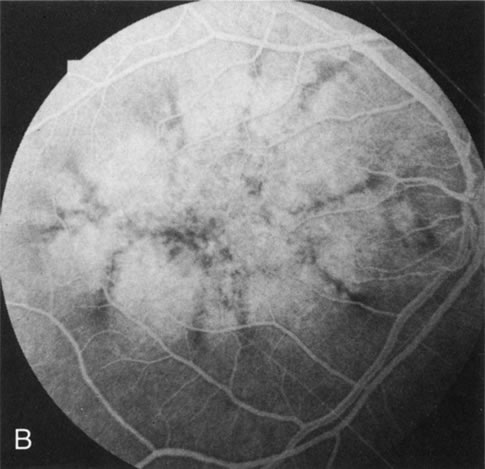

Generalized choroidal dystrophy is usually noted in middle-aged mildly symptomatic individuals who show a predominantly peripapillary or pericentral distribution of choroidal atrophy. Gradually, over the years these areas enlarge to eventually involve the entire retina. These changes are vividly seen on FA (Fig. 6).

Fig. 6. Generalized choroidal dystrophy. This 65-year-old woman gradually developed enlarging, progressive areas of choroidal atrophy over a 20-year period. When initially seen, the abnormalities were confined to the peripapillary and macular region (A,B). In a recent examination, the generalized choroidal atrophy is vividly demonstrated on angiography (C–F).